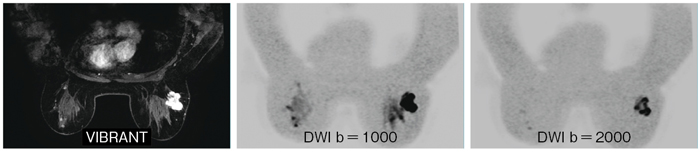

●乳腺ボリュームアプリケーション“VIBRANT-FLEX” & “High b-value DWI”

乳腺の両側3Dダイナミック撮像を行うためのボリュームアプリケーションVIBRANTは,独自のデュアルシム機能の搭載により,両側均一な脂肪抑制を実現します(図1)。さらに,VIBRANT-FLEXでは,フィールドマップを用いることで局所磁場不均一を克服することが可能です。また,乳房自体の形状により,拡散強調画像(以下,DWI)においては,脂肪抑制効果はもちろんのこと,その歪みも問題となりますが,MR750wではb=2000で撮像したDWIも良好な脂肪抑制の下,歪みの少ない画像を提供できます。

図1 GE MRIの乳腺ボリュームアプリケーション(画像ご提供:聖路加国際病院様)